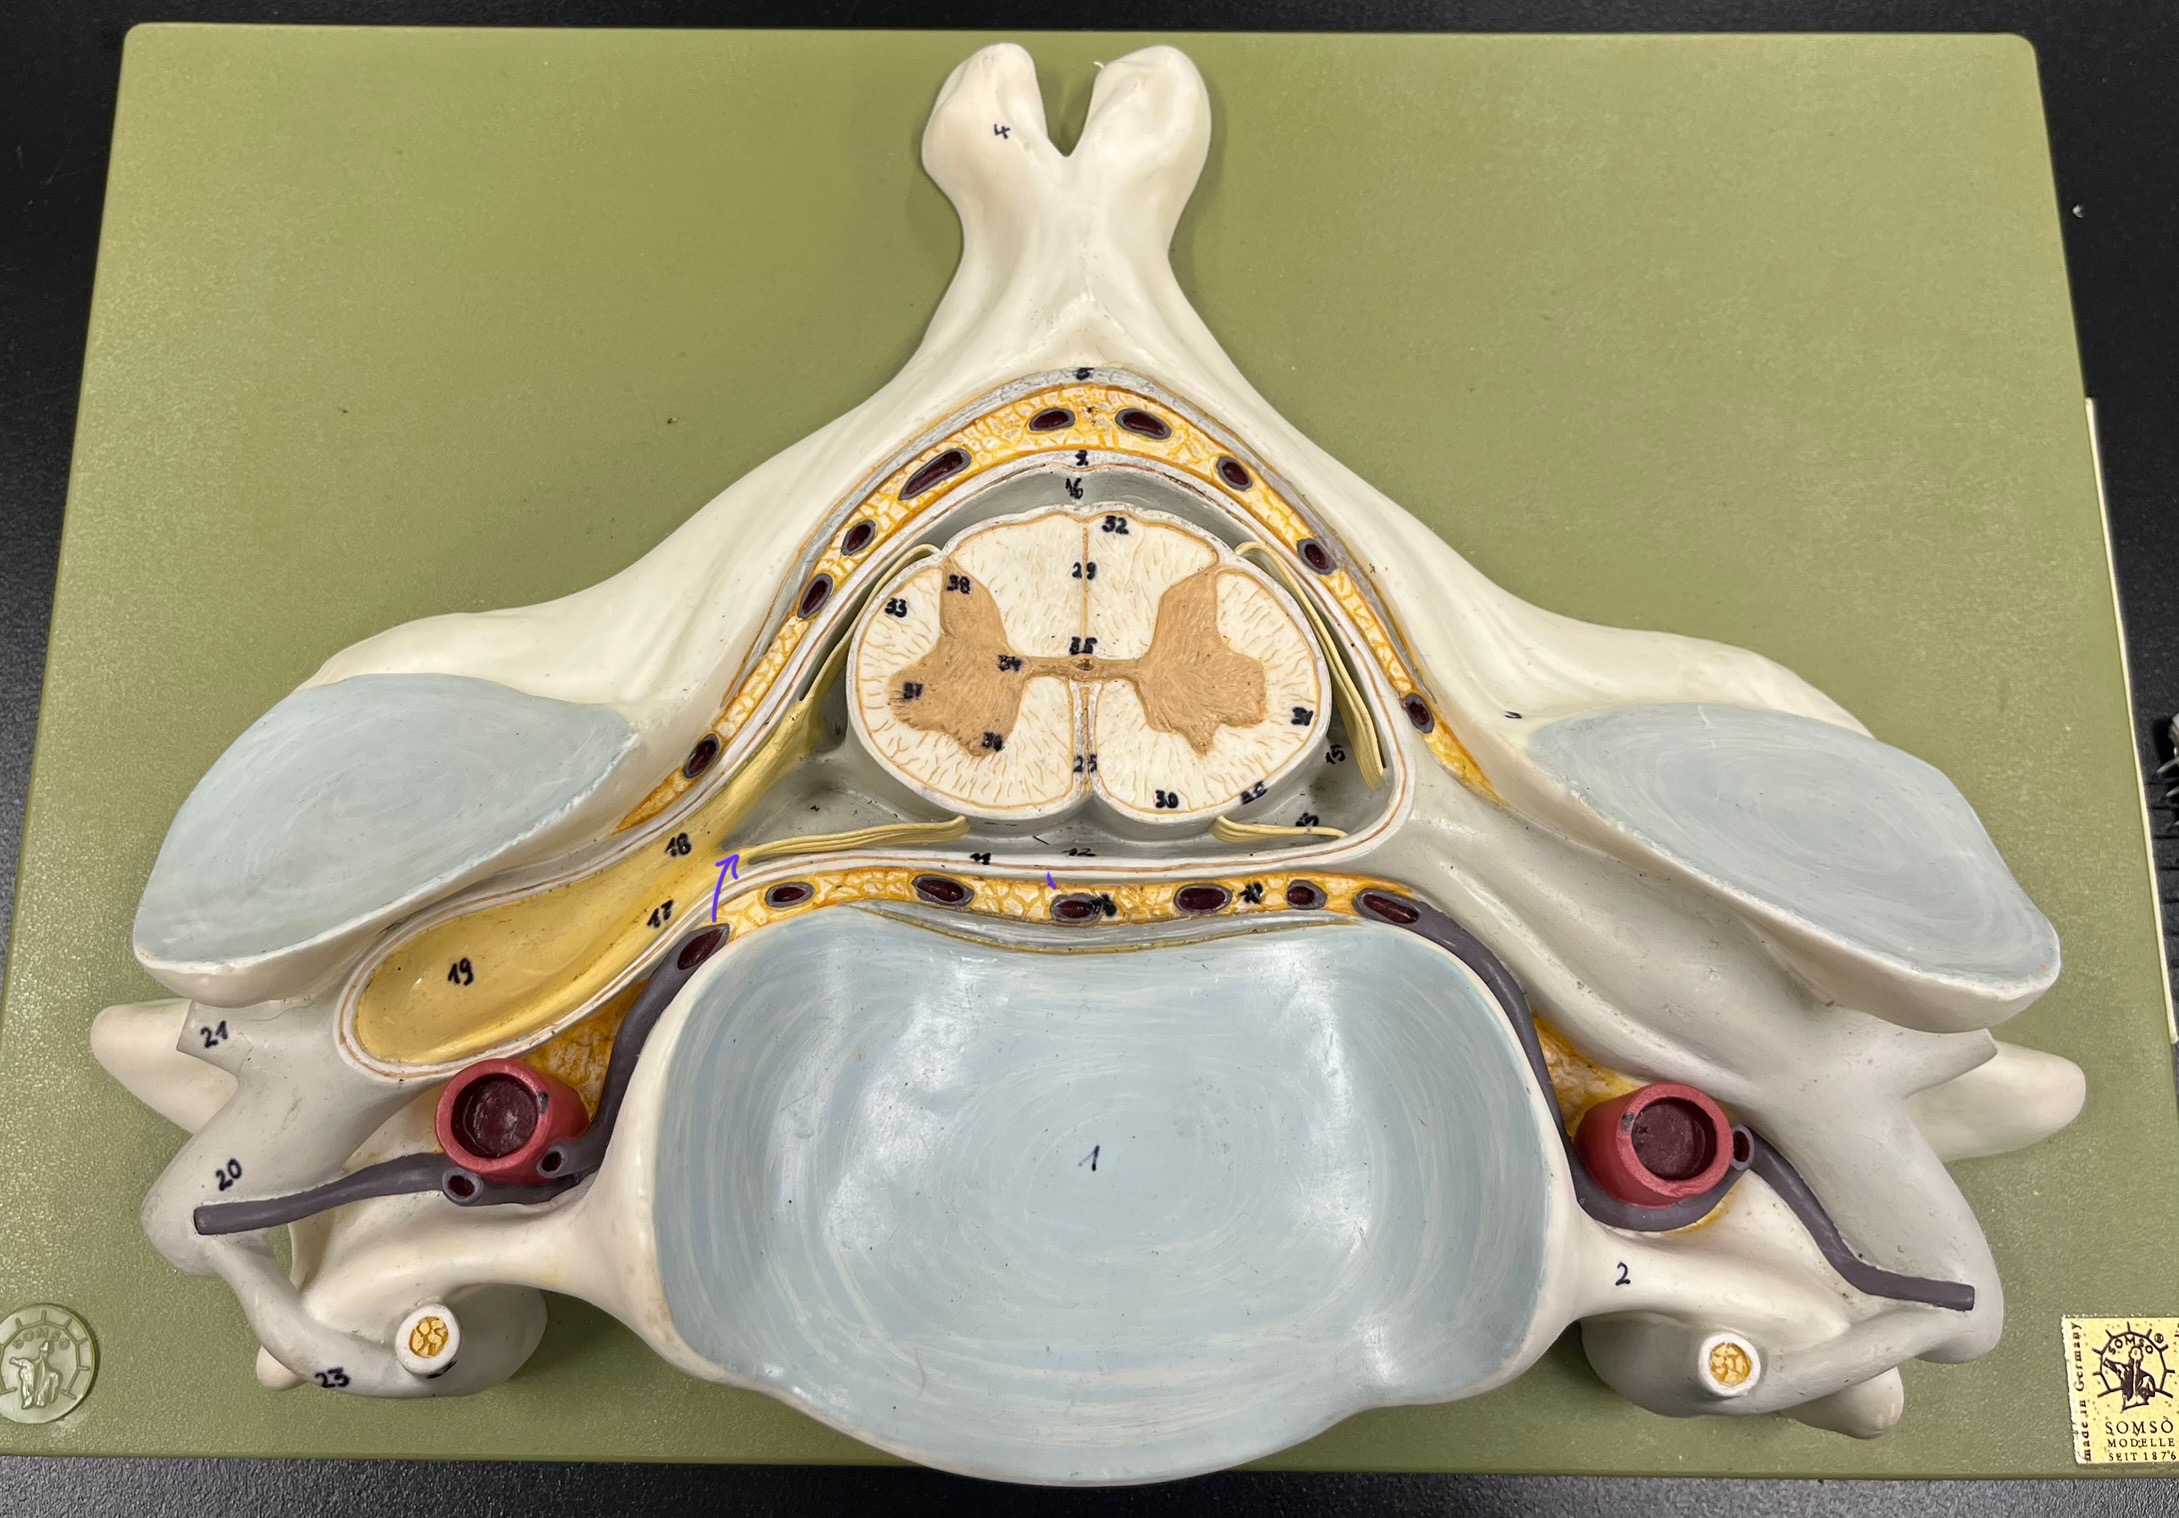

epidural space

dura mater

subdural space

arachnoid mater

subarachnoid space

pia mater

denticulate ligaments

What is the groove here?

anterior median fissure

posterior median sulcus

posterior (dorsal) horn

posterior (dorsal) horn; R—>L

anterior (ventral) horn

lateral horn (selected models)

gray commissure

central canal

anterior column

lateral column

posterior column

white commissure

posterior (dorsal) root ganglion

What is the bulb here?

posterior (dorsal) root ganglion

posterior (dorsal) root

posterior (dorsal) root

anterior (ventral) root

anterior (ventral) root

dorsal ramus

dorsal ramus

ventral ramus

ventral ramus

rami communicantes

rami communicantes

sympathetic chain ganglia

sympathetic chain ganglia